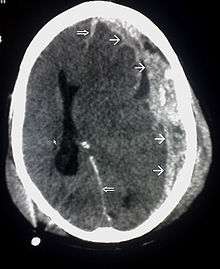

| CT scan showing cerebral contusions, hemorrhage within the hemispheres, subdural hematoma, and skull fractures[1] | |

Traumatic brain injury (TBI), also known as intracranial injury, occurs when an external force traumatically injures the brain. TBI can be classified based on severity, mechanism (closed or penetrating head injury), or other features (e.g., occurring in a specific location or over a widespread area). Head injury usually refers to TBI, but is a broader category because it can involve damage to structures other than the brain, such as the scalp and skull.

One type of focal injury, cerebral laceration, occurs when the tissue is cut or torn.[30] Such tearing is common in orbitofrontal cortex in particular, because of bony protrusions on the interior skull ridge above the eyes.[24] In a similar injury, cerebral contusion (bruising of brain tissue), blood is mixed among tissue.[15] In contrast, intracranial hemorrhage involves bleeding that is not mixed with tissue.[30]

Hematomas, also focal lesions, are collections of blood in or around the brain that can result from hemorrhage.[3] Intracerebral hemorrhage, with bleeding in the brain tissue itself, is an intra-axial lesion. Extra-axial lesions include epidural hematoma, subdural hematoma, subarachnoid hemorrhage, and intraventricular hemorrhage.[31] Epidural hematoma involves bleeding into the area between the skull and the dura mater, the outermost of the three membranes surrounding the brain.[3] In subdural hematoma, bleeding occurs between the dura and the arachnoid mater.[15] Subarachnoid hemorrhage involves bleeding into the space between the arachnoid membrane and the pia mater.[15] Intraventricular hemorrhage occurs when there is bleeding in the ventricles.[31]